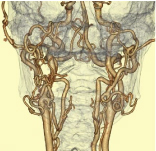

頸部血管VR -

頸部血管MIP -